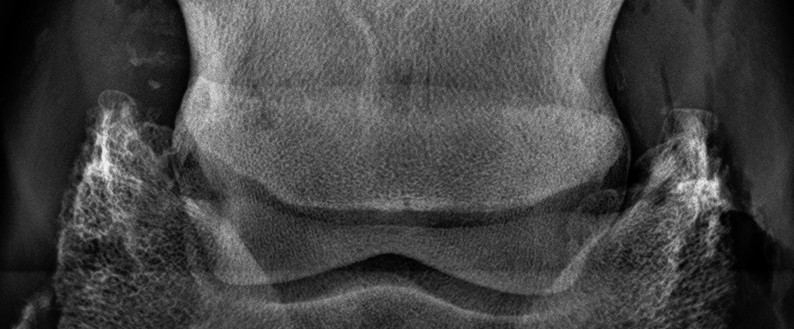

Egészséges nyírcsont. Szabályos határai vannak, egyenletesen sötétszürke színű.

Normális nyírcsont. Jól elkülönülő vékony, fehér kéregállomány és sötétszürke velőállomány, benne vékony csatornácskák.